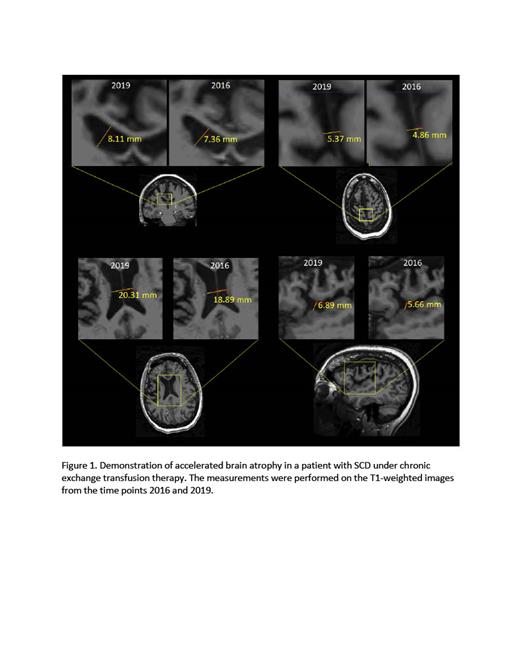

Neurovascular complications are a common and major cause of morbidity and mortality in patients with sickle cell disease (SCD). Prior studies have demonstrated cortical thinness (Kim et al. 2016) as well as reduced cerebral volume in children with SCD (Kawadler et al. 2013) when compared to age-matched controls. There is very limited data regarding cerebral volume in adults with SCD. Recently, our group showed that adults with SCD have reduced cerebral volumes when compared to race and age-matched controls (Santini et al. 2021a). A prior prospective study by Nitkunan et al. 2011. demonstrated brain atrophy rate of −0.914%±0.8% in older adults (mean 68 years old) with Small Vessels Disease, which is about twice the rate of healthy controls. Transfusion therapy has been effective in the primary and secondary prevention of strokes and silent infarcts in SCD. Automated erythrocytapheresis (exchange transfusion), in particular, is the most aggressive disease modifying-treatment in SCD, by rapidly diluting sickle hemoglobin and replacing it with normal hemoglobin. We hereby present a case of a 42 -year-old woman with sickle cell anemia (HbSS) who developed accelerated loss of cerebral volume within a three-year period despite chronic exchange transfusion therapy. The patient underwent brain MRI in 2016 and 2019 as part of an NIH-funded, prospective, longitudinal study of the neuroradiological correlates of cognitive dysfunction in SCD. Past medical history is notable for prior right hemispheric stroke for which she was placed on chronic exchange transfusion monthly with the goal of reducing HbS to <30%. T1-weighted images were acquired at 7T MRI using a customized RF coil (Santini et al. 2021b) and with the following parameters: 3D MPRAGE, TE/TI/TR = 2.17/1200/3000 ms, resolution 0.75 mm isotropic, total acquisition time = 5 min. The extent of atrophy was estimated using the longitudinal analysis as part of the Freesurfer package (version 7.1.1) and ITK-snap (version 3.8.0). The pre-exchange HbS was reliably maintained <30% throughout the observation period, during which the patient did not develop new strokes or neurological complications. Unfortunately, in spite of the patient's excellent adherence with the treatment and the achievement of the target HbS values, we observed progression of cerebral atrophy of 2.47% in volume in the hemisphere contralateral to the stroke between the two time points. The differences are also visible in the raw data (Figure 1). Chronic exchange transfusion is the most aggressive preventive treatment for the neurological sequelae of sickle cell disease. This case demonstrates an accelerated brain atrophy, suggesting that this treatment may not be fully protective against progressive cerebral atrophy. Unfortunately, the mechanism of brain atrophy in SCD is not fully understood. More longitudinal studies are needed to assess cortical changes and cerebral volume changes as this can lead to further understanding of their pathophysiology and to the development of therapeutic options to arrest the progression of cerebrovascular disease in this population.